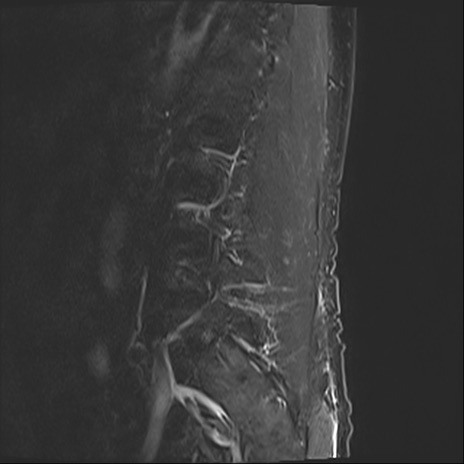

【整形】TIPS症例2 腰椎MRI STIR(矢状断像)

【症例】70歳代男性

【主訴】左下肢痛

【現病歴】2週間前くらいから腰痛、左下肢痛あり。左臀部から大腿、下腿外側のしびれが常時ある。歩行とともに同部位の痛みあり。

【身体所見】Lasegue70-/60+、Bragard-/±、PTR ±/±、ATR -/-、IP 5/5、TA 5/4、TS 5/5、EHL 右第1足趾なし/3、FHL 5/5、hypersthesia(-)、足背動脈触知良好

異常所見と診断は?